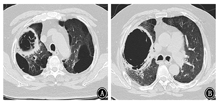

患者短期内双肺出现散在斑片影及斑点影,伴大小不等空洞,考虑肺部感染性疾病。入院后给予比阿培南(0.6 g,静脉滴注,2次/d)+万古霉素(0.5 g,静脉滴注,每8小时1次)联合抗细菌,继续醋酸泼尼松40 mg/d口服抗炎,并给予多索茶碱静脉滴注、雾化吸入布地奈德及特布他林平喘,氨溴索静脉滴注化痰,皮下注射胰岛素控制血糖等治疗。完善相关检查,ESR为47 mm/h;C反应蛋白96.10 mg/L;生化:钾4.0 mmol/L,钠131.0 mmol/L,氯96.0 mmol/L,空腹血糖17.0 mmol/L,尿素7.1 mmol/L,肌酐68.0 μmol/L,丙氨酸氨基转移酶29.0 U/L,天门冬氨酸氨基转移酶13.0 U/L,乳酸脱氢酶253 U/L,肌酸激酶79 U/L,总蛋白51.1 g/L,白蛋白30.8 g/L。尿常规:葡萄糖++++;血结核菌38kD蛋白阴性,结核菌外膜抗体阳性;结核菌素试验阴性;降钙素原、抗链球菌O、类风湿因子、自身抗体系列、肿瘤相关抗原系列、粪常规均正常。术前四项(乙肝表面抗原、丙肝抗体、人类免疫缺陷病毒抗体、梅毒血清特异性抗体)阴性。心电图大致正常。心脏超声:主动脉瓣钙化,左室后壁运动幅度稍减低,左室舒张功能减低。腹部超声:脂肪肝,余未见异常。肺功能:第1秒用力呼气容积/FVC为43.22%,第1秒用力呼气容积占预计值百分比为24.9%,提示阻塞性通气功能障碍,小气道功能障碍,残气量/肺总量轻度增高,弥散功能重度减低。痰涂片找抗酸杆菌阴性(3次)。患者入院当日(2018年1月26日)发热,最高体温达38 ℃;1月27日体温正常;1月28日再次发热,最高体温达38.1 ℃;1月29日之后未再发热,憋喘较前略好转,痰中带血减少。1月29日痰涂片:革兰阳性球菌可见;痰真菌培养:白色假丝酵母菌+。1月30日血1,3-β-D葡聚糖检测(G试验):247.3 μg/L(升高);血常规:白细胞计数12.56×109/L,红细胞计数5.00×1012/L,血红蛋白143 g/L,血小板计数179×109/L,中性粒细胞比例85.3%,淋巴细胞比例7.6%;C反应蛋白55.10 mg/L;血气分析:pH值7.43,PaCO2为48.4 mmHg,PaO2为81.6 mmHg,SaO2为95.8%。入院后每日皮下注射胰岛素累积剂量56 IU。1月26日至1月30日血糖控制不理想,空腹血糖波动于11~18 mmol/L,早餐及午餐后2 h血糖波动于10~18 mmol/L,晚餐后2 h血糖波动于15~21 mmol/L。患者痰检见白色假丝酵母菌+,G试验轻度增高(近期有应用哌拉西林舒巴坦钠史,不排除干扰),近期有糖皮质激素应用史,血糖控制欠佳,综合以上因素,考虑肺真菌感染不排除。1月30日给予伏立康唑200 mg口服抗真菌,每12小时1次(第1个24小时400 mg/次),同时减量醋酸泼尼松为30 mg/d。2月2日痰真菌培养:曲霉菌属+(2次),白色假丝酵母菌+,进一步支持真菌感染,建议行气管镜检查,患者因喘憋不适,一直不同意。之后又有2次痰培养:曲霉菌属1~2个菌落。2月5日患者憋喘较重,复查血常规:白细胞计数23.32×109/L,红细胞计数5.22×1012/L,血红蛋白151 g/L,血小板计数208×109/L,中性粒细胞比例92.2%,淋巴细胞比例3.7%;C反应蛋白229.80 mg/L;血气分析:pH值7.44,PaCO2为47.3 mmHg,PaO2为82.3 mmHg,SaO2为95.7%,提示感染加重。2月5日伏立康唑改为0.3 g,静脉滴注,每12小时1次。2月6日胸部CT示双肺散在斑片影及斑点影,伴大小不等空洞,与1月26日胸部CT比较右肺上叶空洞增大,右肺上叶病变进展(图3)。继续伏立康唑静脉滴注抗真菌,比阿培南联合万古霉素抗细菌治疗。2月12日胸部CT示右肺上叶空洞较2月6日进一步增大(图4)。2月12日血气分析:pH值7.45,PaCO2为57.2 mmHg,PaO2为78.3 mmHg,SaO2为95.1%。经反复动员,2月13日患者同意气管镜检查,结果(图5)示主气管黏膜表面可见白色分泌物附着;左上叶支气管黏膜充血明显,可见大量脓性分泌物;右上叶支气管各叶段开口变窄,以右上叶尖段开口变窄明显;右上叶支气管黏膜充血水肿明显,活检或刷检易出血。气管镜刷片及灌洗液病理见少许坏死物及中性粒细胞,未见肿瘤细胞。支气管镜肺活检(右上叶)病理:送检肺组织慢性炎,肺间质可见单核细胞浸润,纤维组织增生,肺泡上皮增生,肺组织表面附着成团的坏死物,坏死物中可见真菌菌丝及孢子。气管镜刷片培养:曲霉菌属1个菌落;气管镜后痰培养:曲霉菌属4个菌落。患者IPA诊断依据充足,应用伏立康唑效果差,2月14日改为两性霉素B脂质体静脉滴注,从10 mg/d始,逐日递增,增至150 mg/d时患者精神萎靡、憋喘、乏力、纳差、尿少、肾功能异常,尿素18.5 mmol/L,肌酐166 μmol/L,总蛋白45.6 g/L,白蛋白26.9 g/L。2月18日血气分析:pH值7.38,PaCO2为55.4 mmHg,PaO2为72.4 mmHg,SaO2为93.5%。考虑患者对该药不良反应较大,停用两性霉素B脂质体。2月19日给予伏立康唑(0.3 g,静脉滴注,每12小时1次)联合卡泊芬净(50 mg/d,静脉滴注)抗曲霉菌治疗。2月20日后患者多次血气分析示PaCO2升高,波动于56~79 mmHg,PaO2低,波动于50~80 mmHg,给予保肾、人血白蛋白支持、无创呼吸机辅助通气等治疗。口服泼尼松经逐渐减量,于2月17日后停用。住院期间患者一直纳差,进食量少,尽管每日皮下注射胰岛素累积剂量60 IU,但血糖仍控制不理想,空腹血糖波动于12~20 mmol/L,餐后2 h血糖波动于14~26 mmol/L;自停用泼尼松后,血糖逐渐好转,空腹血糖波动于8~10 mmol/L,餐后2 h血糖波动于11~14 mmol/L。3月6日血气分析:pH值7.35,PaCO2为55.4 mmHg,PaO2为72.4 mmHg,SaO2为93.5%。3月6日胸部CT示双肺多发空洞,右肺上叶空洞较前增大,双肺病变继续进展(图6)。治疗效果不理想,家属要求转院。